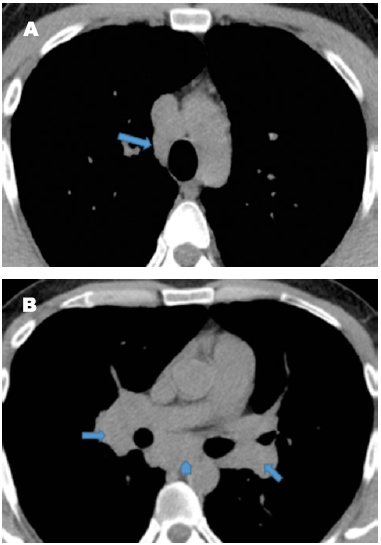

La presentación más común de la sarcoidosis corresponde a la presencia de adenopatías paratraqueales derechas e hiliares bilaterales y simétricas. Las adenopatías hiliares bilaterales, solas o en combinación con adenopatías mediastinales, se presentan aproximadamente en un 95 % de los pacientes con sarcoidosis (25,31); las adenopatías paratraqueales izquierdas, subcarinales, ventana aortopulmonar y prevasculares están presentes hasta en 50 % de los pacientes (28). Las calcificaciones de las adenopatías están directamente relacionadas con la duración de la enfermedad granulomatosa. Se ven en el 3 % de los pacientes después de 5 años y en el 20 % después de 10 años; pueden tener varias apariencias: amorfas, punteadas, forma de crispeta o en cáscara de huevo.

En cuanto a la afectación del parénquima pulmonar, lo característico es la distribución perilinfática de lesiones micronodulares (del 75-90 % de los casos), con una distribución bilateral y simétrica predominantemente, aunque no de forma invariable en las zonas medias y superiores. Estos nódulos se encuentran usualmente en el intersticio peribroncovascular, subpleurales y septos interlobulillares, pueden coalescer en el tiempo formando lesiones de mayor tamaño (macronódulos) (Figura 3). Los granulomas sarcoides también causan con frecuencia engrosamiento nodular o irregular del intersticio peribroncovascular (29,30).